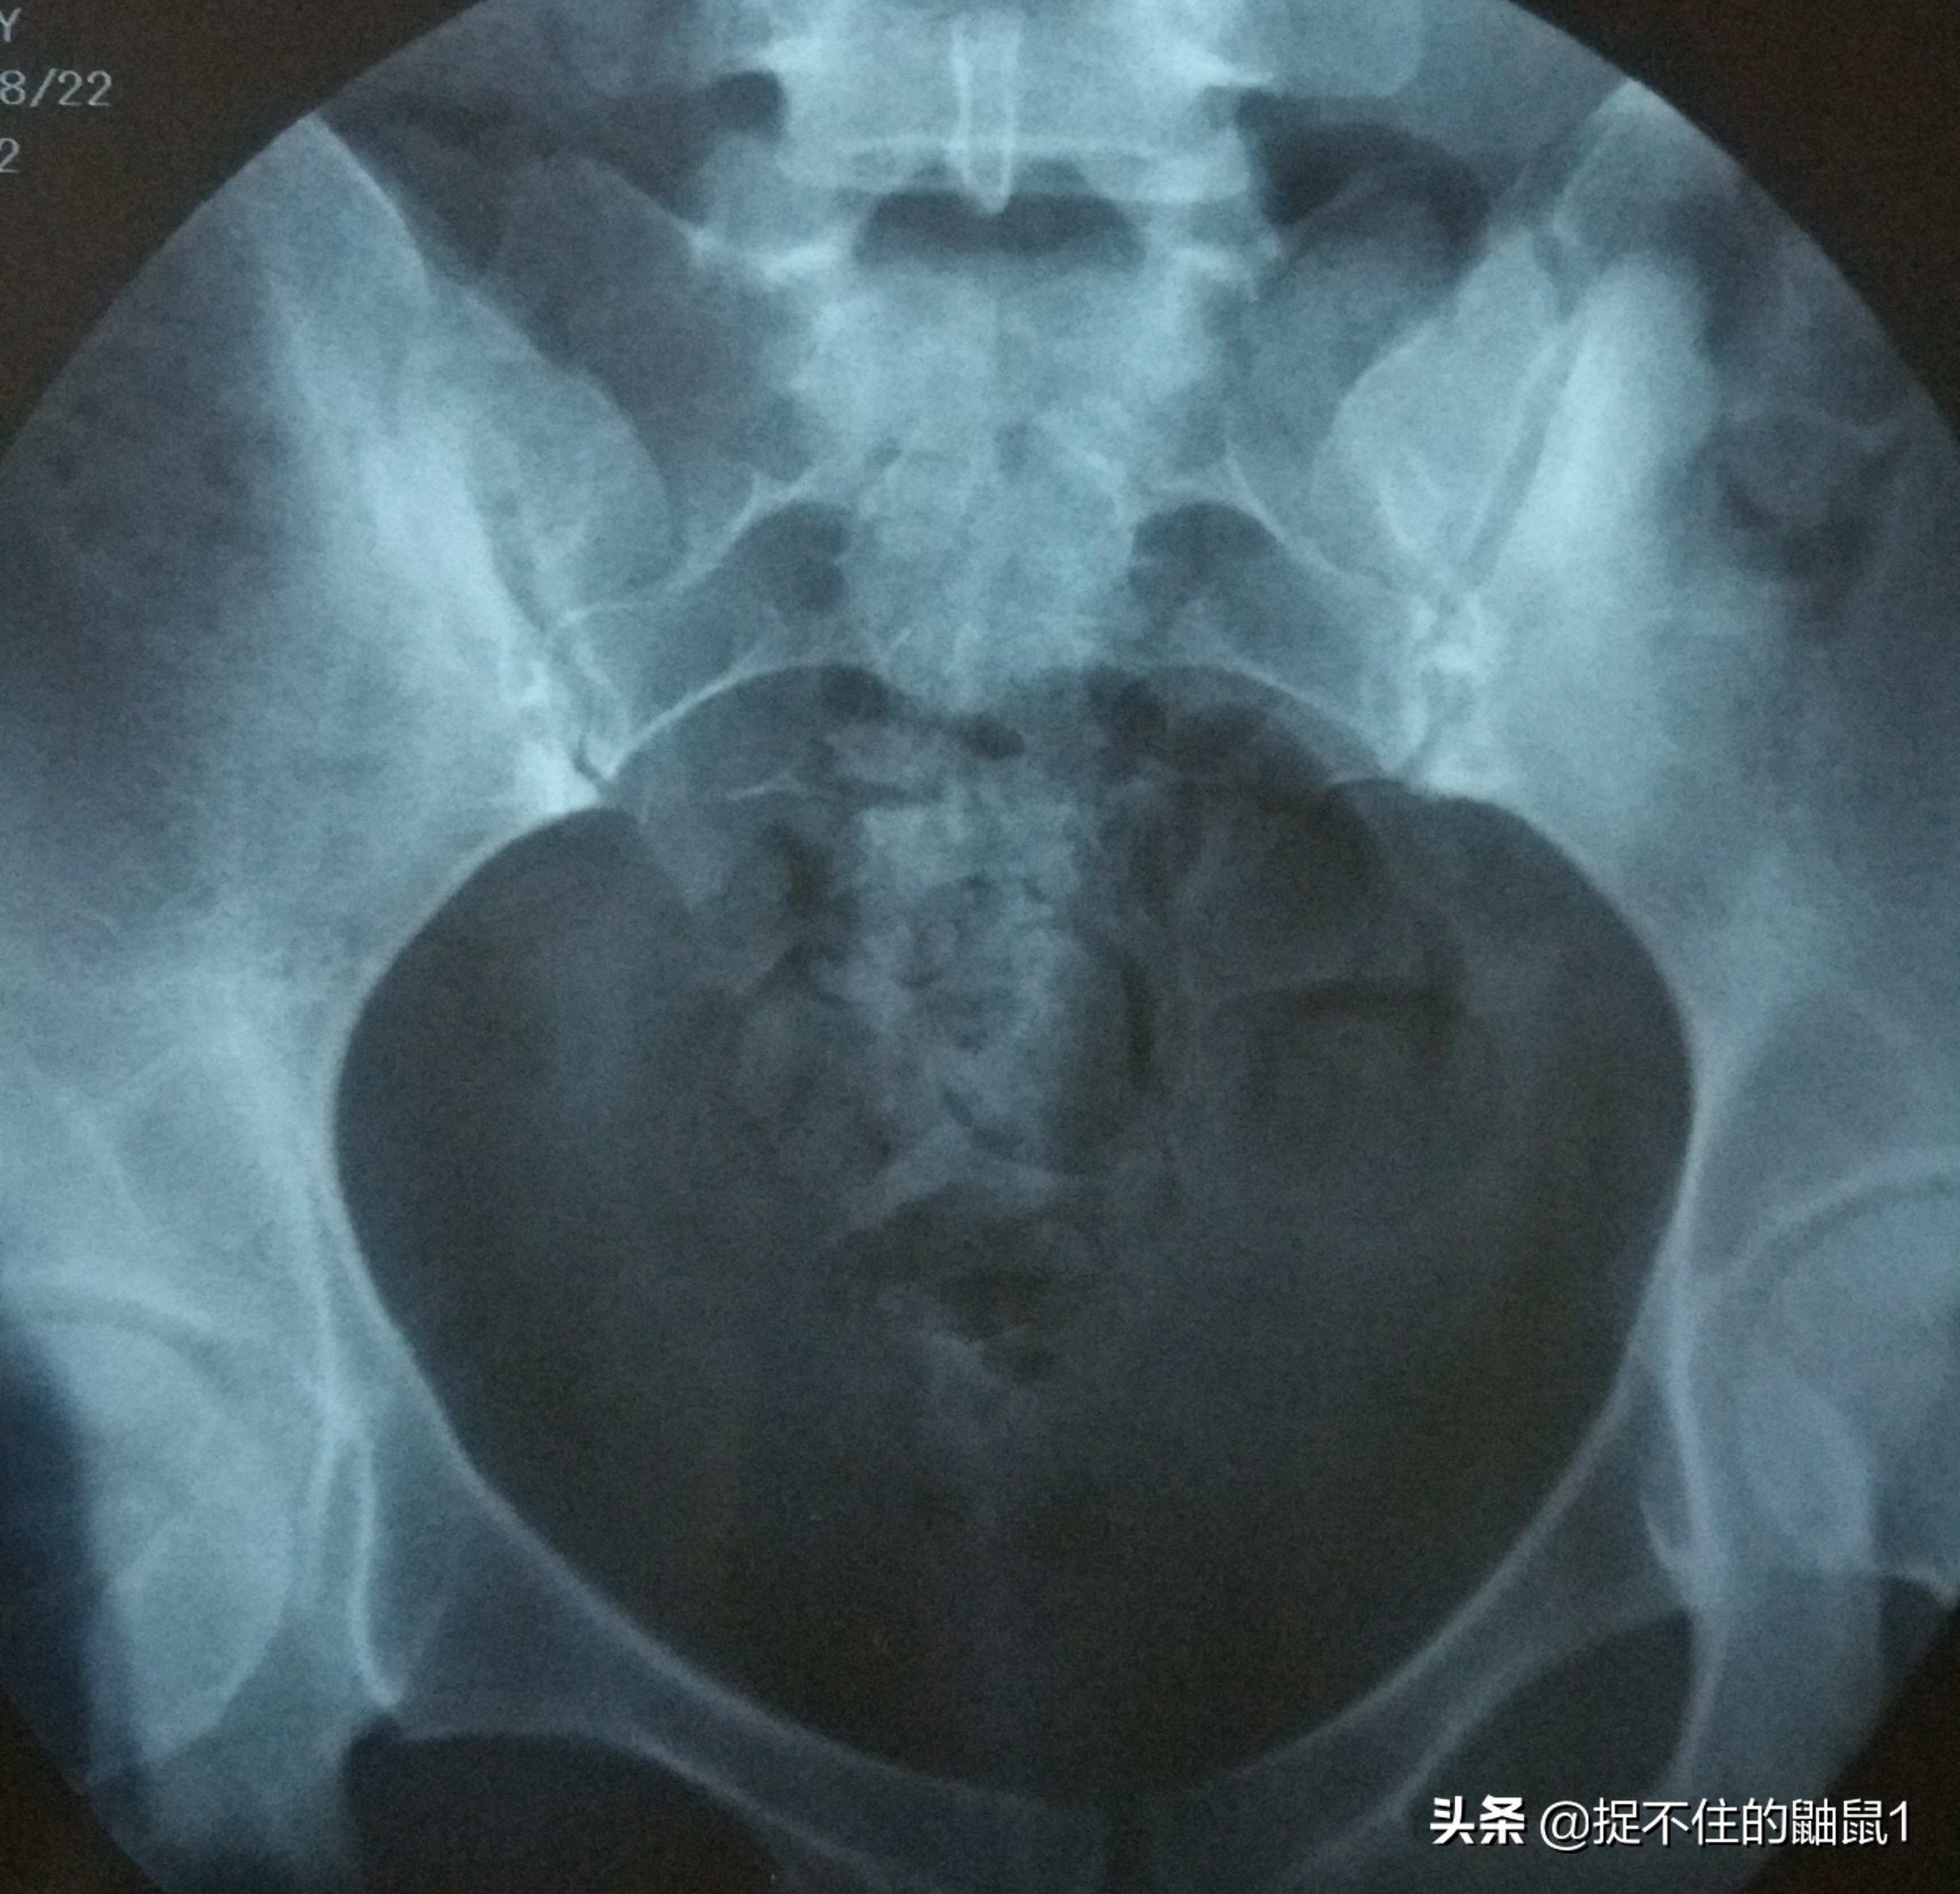

这是造影片子,发亮的是碘油,这是推入当天的造影

这是第二天碘油弥散后的造影,没弥散开,就是输卵管不通,这是医生跟我说的,我也看不懂